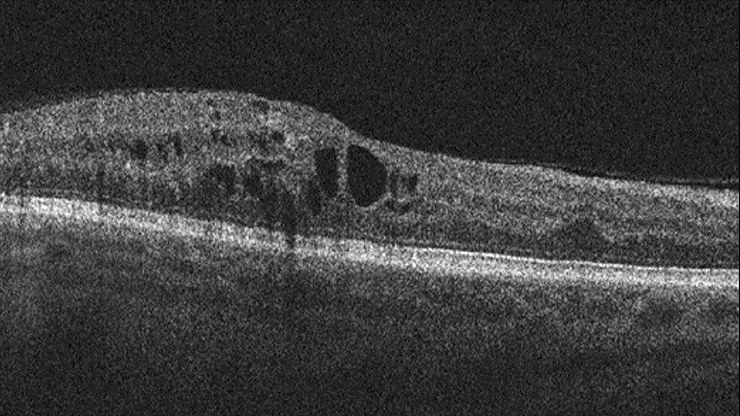

Although CFP provides valuable information, the gold standard for diagnosing DME and determining the need for treatment is optical coherence tomography (OCT), which takes a three-dimensional measurement of the macula, the middle part of the retina that increases in thickness with the progression of DME. However, OCT is often unavailable in screening programmes due to cost and technical limitations. A thickness of 250 microns is considered the threshold for the condition, whereas 400 microns is the point at which many ophthalmologists recommend starting treatment.

Our team decided to explore whether we could use deep learning to teach computers how to estimate macular thickness from CFP images, making DME diagnosis easier for patients and ophthalmologists. Currently, CFP images are interpreted by specialists who develop the ability over years to gauge the retina’s thickness from the features they see on its surface, but still need to rely on OCT for confirmation and measurement. Our team wanted to generate similar ability in an automated system.

In deep learning, a computer trains itself to detect patterns and relationships in a set of training data, using hundreds of layers of analysis that each pick up different relevant features in an image without any guidance from a user. The system then applies its knowledge to novel input data of the same type. In this case, we gave our computers a large set of CFP and OCT data from participants in two large DME clinical trials to train on.

The deep learning system examined a total of 17,997 CFP images from ~700 patients and compared them with corresponding OCT thickness measurements. The best model we developed using this training set was able to predict macular thickness greater than the 250 micron threshold with an accuracy of 97 percent — an impressive level of performance. Deep learning could even do a reliable job of predicting the actual OCT measurement of the macula’s thickness from a CFP image if it was of sufficient quality.

To test that finding, we still need to validate our system by testing it on other datasets. But presuming it works well, this tool could be of tremendous value to ophthalmologists as they treat patients with diabetes and DME. Once DME patients begin treatment, for example, many of them have to be seen every four weeks for OCT testing to ensure that their condition is not progressing. AI might enable people to use a cell phone camera to monitor their retinal tissue in real time, making it much easier for doctors to keep track of their patients’ need for and response to treatment. We could even envision an app to assess whether treatment is working. Such an innovation would not only be more convenient for patients, but also make them much more active participants in their own care. For ophthalmologists, the ability to estimate macular thickness with CFP would make it easier to identify the most urgent cases and treat them quickly and appropriately.